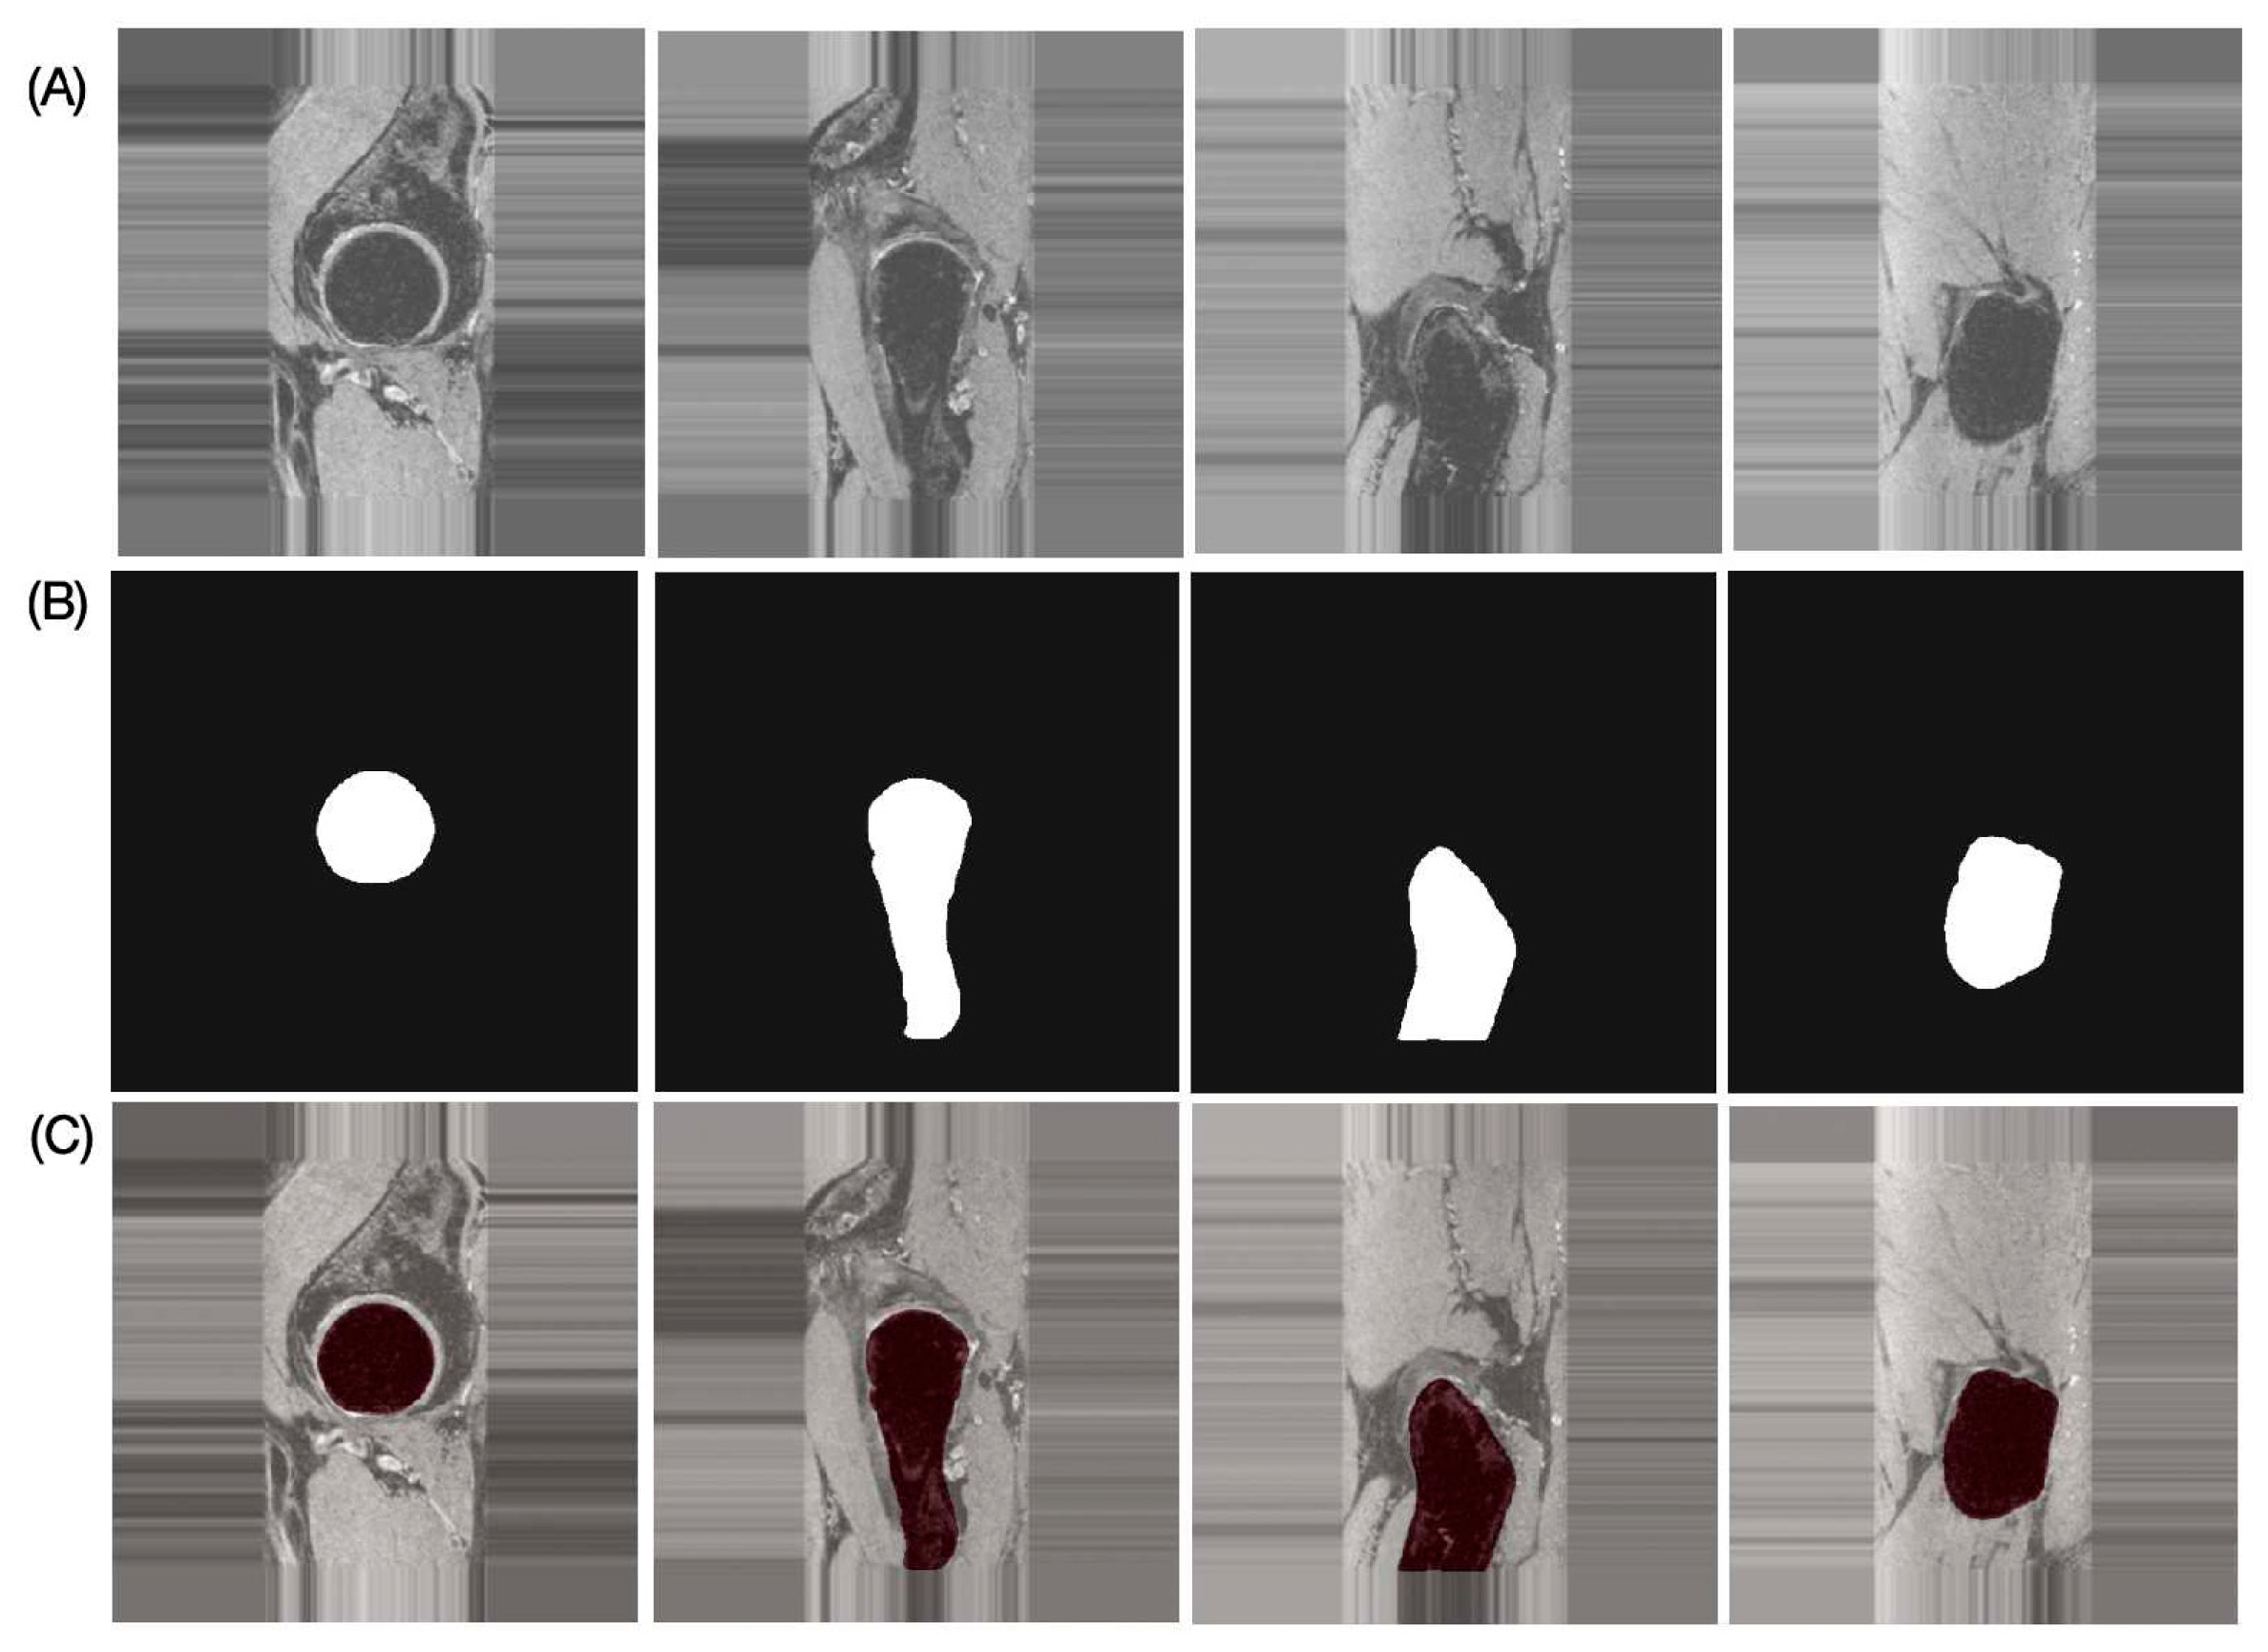

The results of the performance evaluation metrics for inter-reader variability between FG and JL using the left and right hip side data of one subject with 180 images are as follows: DSC = 97.91%, RAVD = 1.43%, ASSD = 0.13 mm, and HD = 2.19 mm. The performance metrics of the proposed automatic bone segmentation method using the final model (model-2) in 10 subjects (20 hips), along with 95% confidence intervals, are as follows: DSC = 96.48% (95% CI: 96.33–96.64), RAVD = 1.13% (95% CI: 0.69–1.57), ASSD = 0.32 mm (95% CI: 0.29–0.35 mm), and HD = 4.66 mm (95% CI: 3.80–5.51 mm). Figure 4 presents representative automatic segmentation results of a selected patient (left hip) across selected slices.

Figure 4.

Representative proximal bone segmentation results for single subject. (A) Original images, (B) corresponding segmentation masks, and (C) segmentation results overlaid on original images.